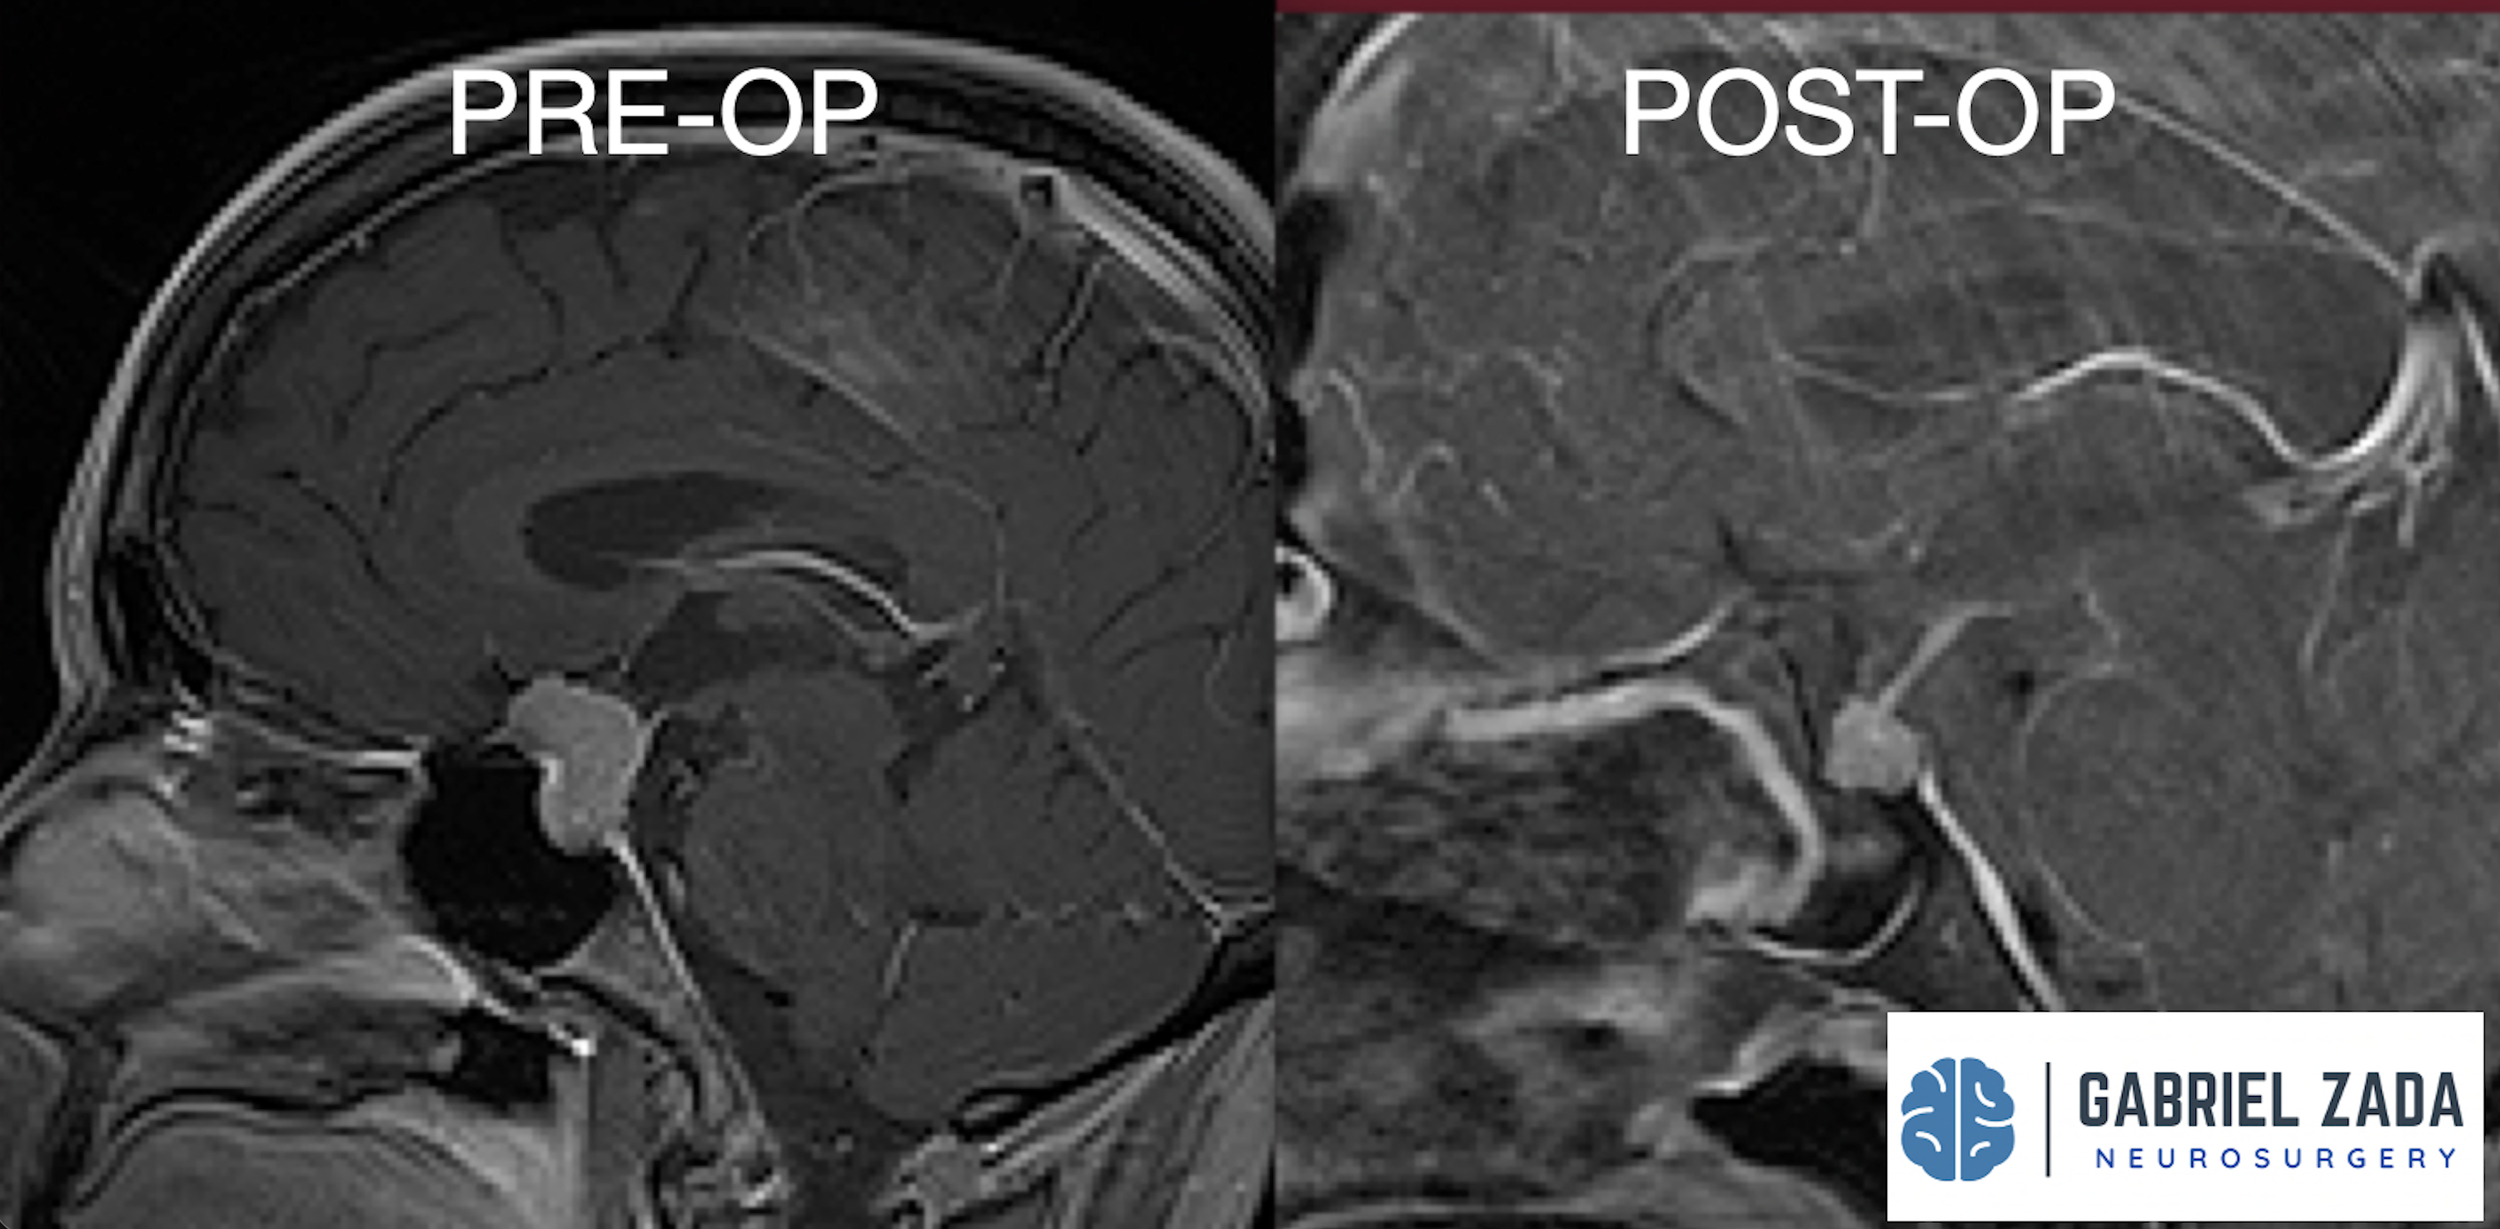

Explore this comprehensive gallery featuring pre‑ and post‑operative imaging of patients with skull‑base tumors treated by Gabriel Zada, MD, MS, FAANS, FACS. These cases highlight Dr. Zada’s expertise in advanced neurosurgical techniques and outcomes.

*Representative cases shown for educational purposes. All images de-identified. Individual results vary.